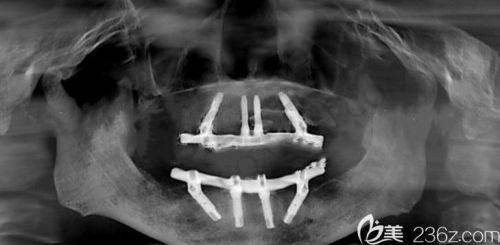

all - on - 4 半口种植牙技术是一种精良的口腔种植解决方案。传统的半口种植牙可能需要植入多颗种植体来支撑牙冠,而 all - on - 4 技术仅需在半口植入 4 颗种植体,通过倾斜其中两颗种植体,利用有限的骨量来固定牙桥。这样一来,大大减少了种植体的植入数量,缩短了手术时间,降低了患者的痛苦和经济负担。同时,这种技术可以实现即刻负重,患者在种植手术后当天就可以戴上临时牙冠,修复部分咀嚼功能,无需长时间等待种植体与牙槽骨完全愈合。